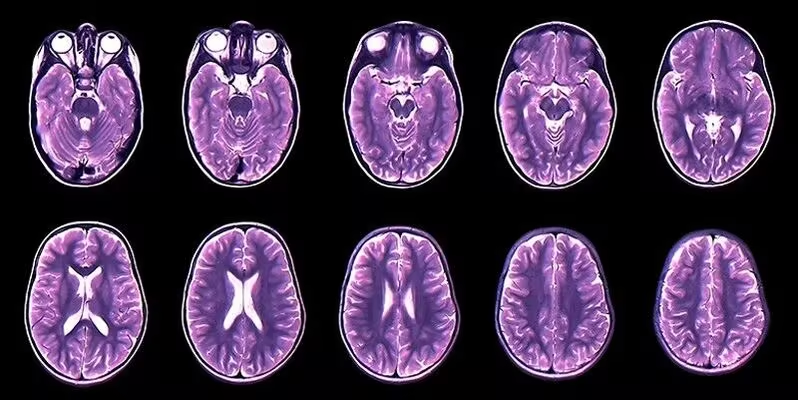

1. Brain Tumor(MRI)Detection 脑肿瘤影像数据集

Brain Tumor(MRI)Detection 是一个用于检测是否有脑肿瘤的医学影像分类数据集,旨在为机器学习模型提供用于脑肿瘤检测任务的 MRI 图像样本。该数据集由磁共振成像(MRI)图像构成,图像被划分为含有脑肿瘤的病例和不含脑肿瘤的正常病例两类。

数据集示例

2. BRISC 2025 脑肿瘤 MRI 分割与分类数据集

BRISC 2025 是一个用于脑肿瘤分割与分类的磁共振成像(MRI)数据集,该数据集同时支持两类任务:一是分类任务,即基于 MRI 图像的多类肿瘤识别;二是分割任务,即利用配对的 MRI 图像与掩模进行像素级肿瘤区域检测。其组织结构清晰,图像与掩模文件名严格对齐,便于直接应用于深度学习模型的训练与验证。